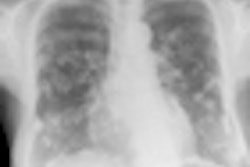

The analysis concluded that "parametric mapping based on DCE-MRI in MPM depicts not only the lesion and its extent, but can map out the heterogeneity of microcirculation within the full thoracic extent of MPM."

The technique shows its best results when the protocol includes shallow breathing, shorter image acquisition time, and adjusting the contrast injection rate to compensate for respiratory and cardiac motion during repetitive image acquisitions. The technique provides a noninvasive insight into tumor microcirculation and vascular permeability, as had been anticipated, prior to and during therapy.